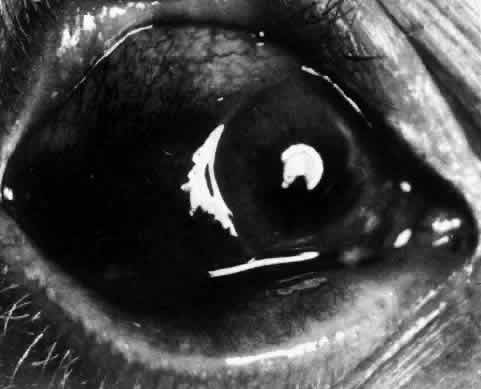

Necrotizing anterior scleritis without adjacent inflammation appears to be a well-defined condition with little relation in clinical features to necrotizing scleral disease, even though the pathology is similar and the final result is the same. Scleromalacia perforans is characterized by the almost total lack of any symptoms. It occurs almost exclusively in patients with long-standing polyarticular rheumatoid arthritis, the majority of whom are female (Figs. 49 and 50; Color Plate 1E).

Fig. 49. A white necrotic plaque developing in an area of sclera with practically no surrounding inflammation in a 60-year-old woman who had had Crohn's disease for 17 years.

Fig. 50. Scleromalacia perforans after treatment. The very thin sclera is covered by conjunctiva only and a few remaining large blood vessels. (Courtesy of Mr. HE Hobbs)

The anterior sclera loses its covering of episclera and develops an area of yellow-white necrotic slough over many months; this eventually separates or is absorbed, leaving the underlying choroid covered by either conjunctiva or nothing at all. As with necrotizing disease, the choroid does not bulge into this ectatic area; but unlike necrotizing disease, spontaneous healing of even small perforations is very limited once the necrotic tissue has been removed (see Fig. 50).

Fluorescein angiography is not helpful, except to indicate areas of vascular closure in an otherwise extremely thin, atrophic episcleral tissue.4 The formation of a sequestrum appears to be caused by arteriolar closure as opposed to the venular disease seen in the other forms of necrotizing scleritis.